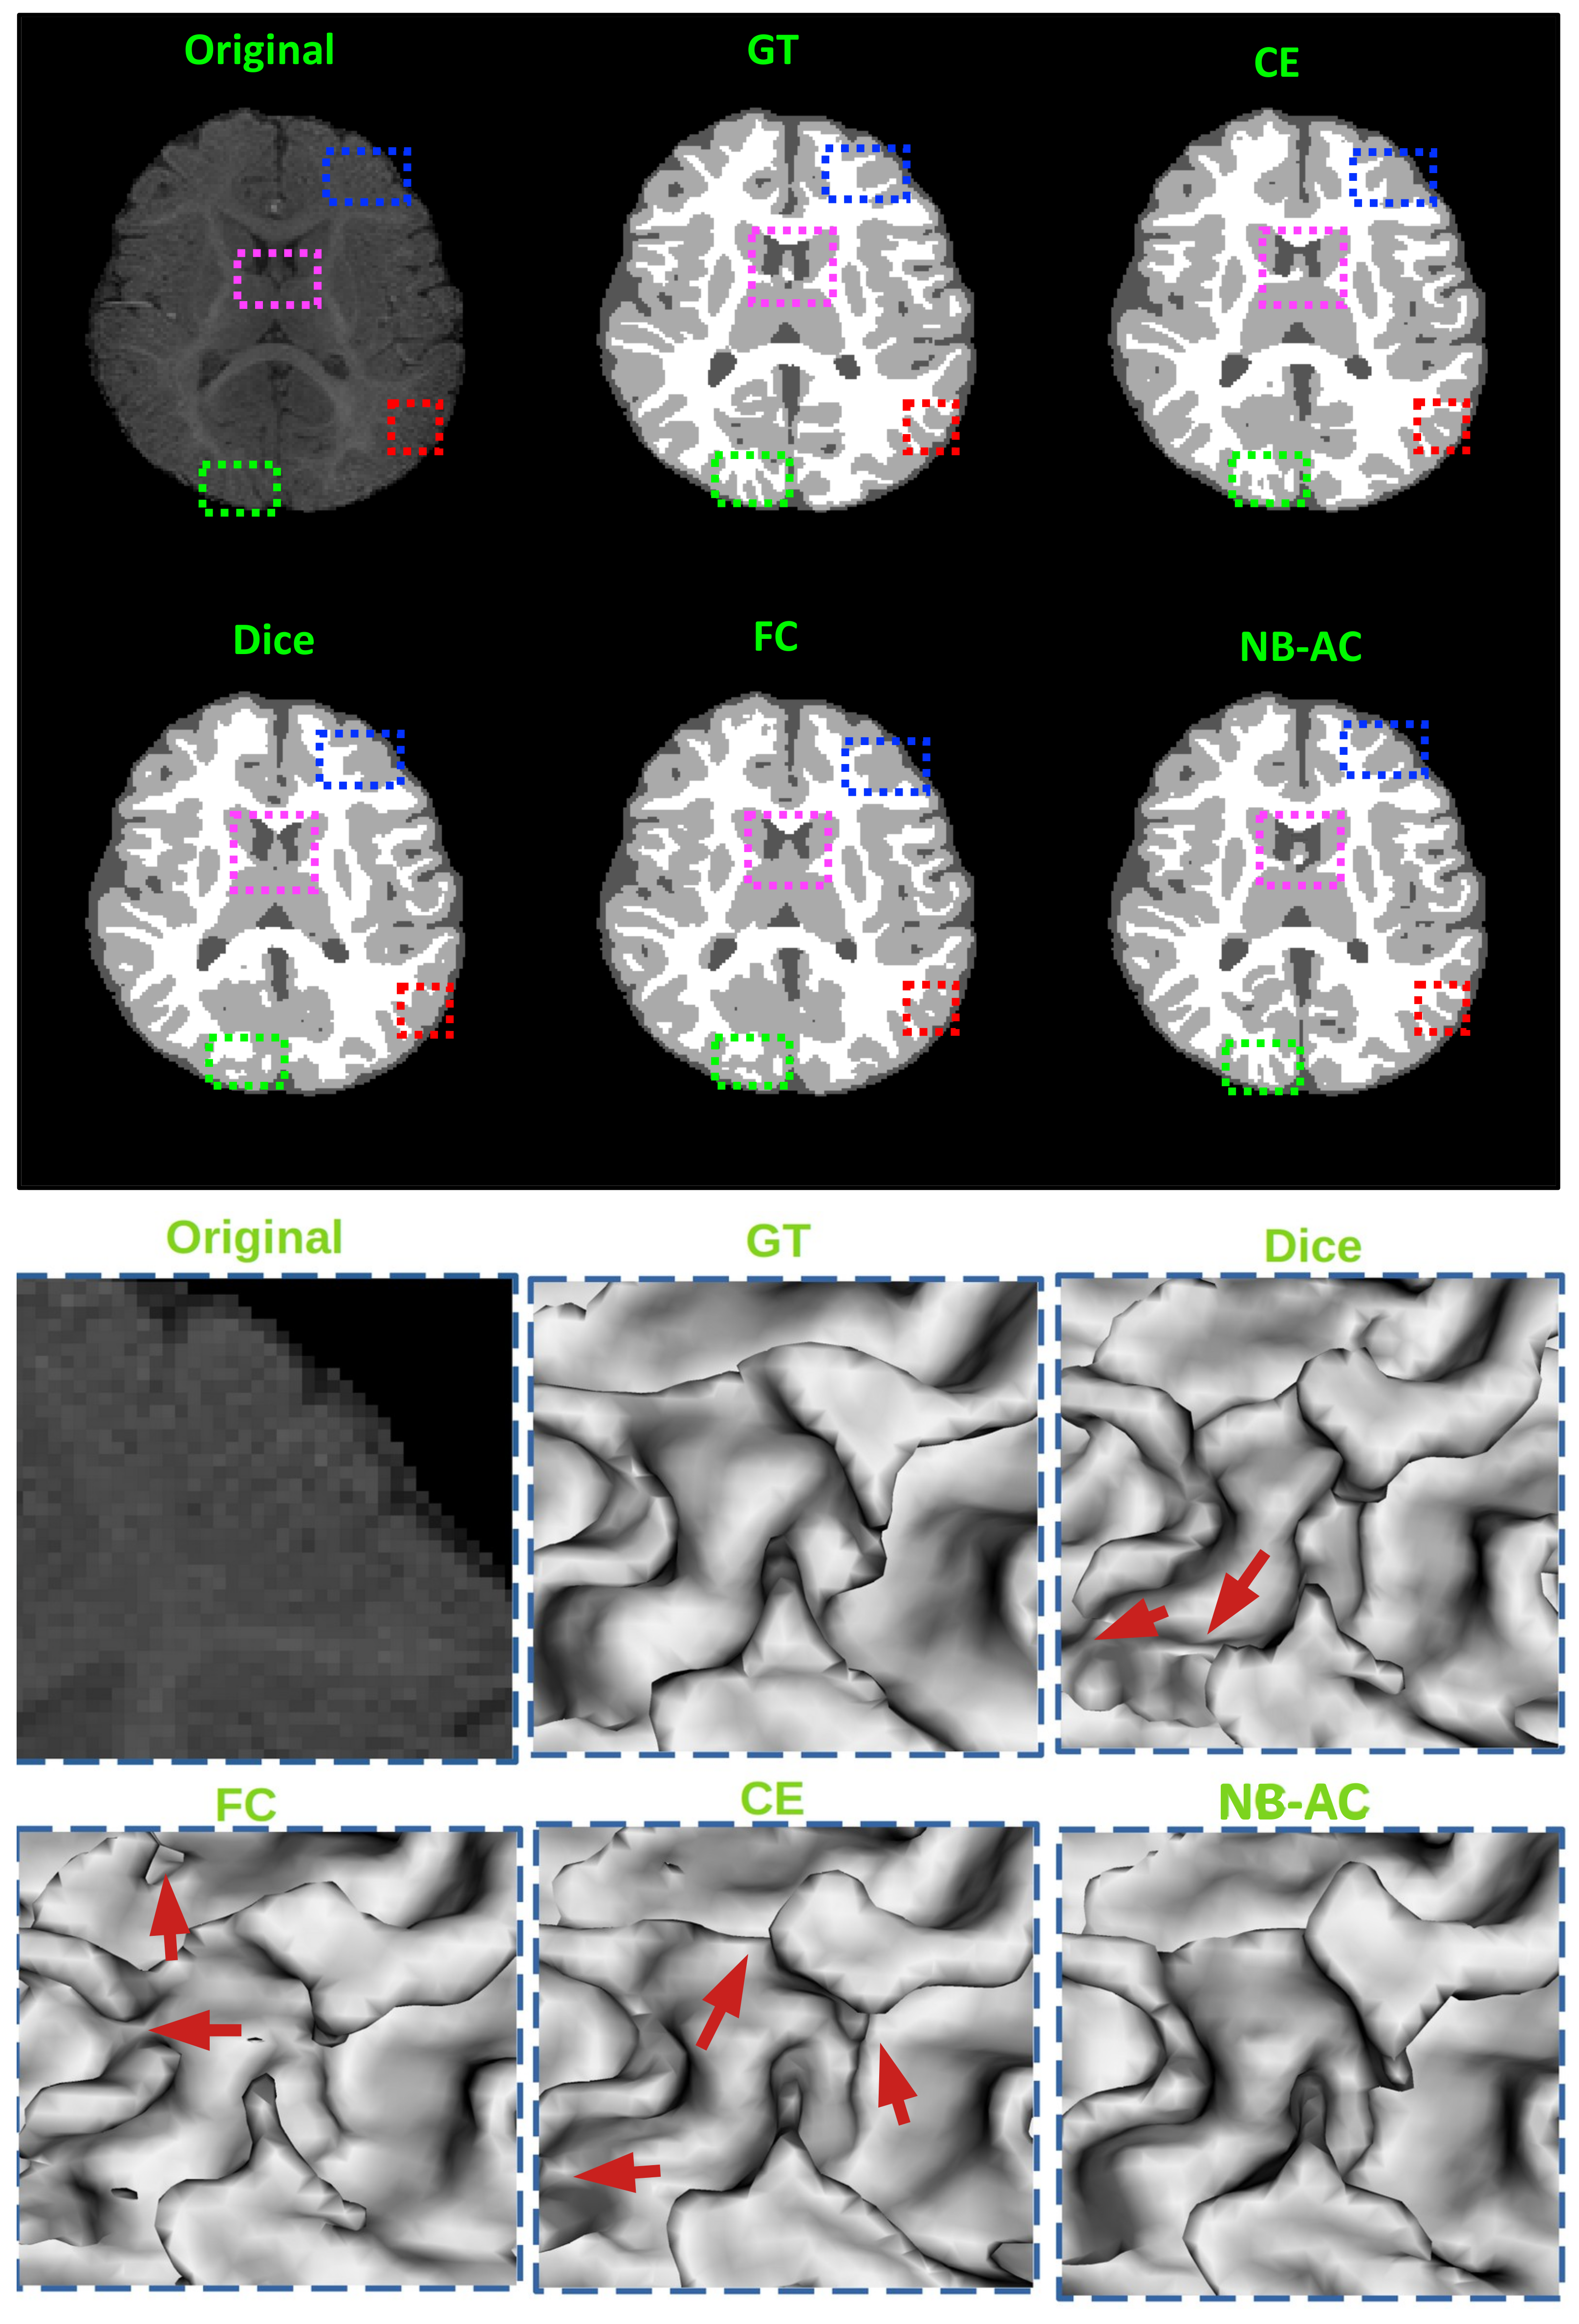

4.4. Results and Comparison